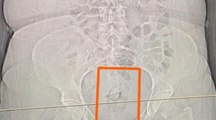

AĞRI'da polisin şüphelenerek hastanede muayene ettirdiği İran uyruklu bir kişinin midesinde 3 paket halinde 124,9 gram metamfetamin, 4,65 grak reçine esrar bulundu. Adliyeye çıkarılan şüpheli tutuklandı.